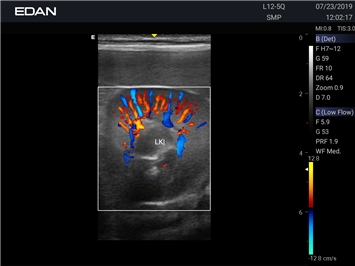

EDAN Acclarix AX2 VET

Ветеринарный ультразвук одним нажатием. Система Acclarix AX2 VET разработана с целью обеспечить бескомпромиссную производительность по доступной цене. Наличие уникальных двойных аккумуляторов в легком корпусе массой 4,5 кг из магниевого сплава позволяет системе Acclarix AX2 VET удовлетворять все потребности ветеринарных исследований, сохранив низкую стоимость.

EDAN Acclarix AX2 VET представляет собой специализированную ветеринарную ультразвуковую систему, сочетающую высокую производительность с доступной ценой. Благодаря продуманной конструкции и передовым технологиям, система обеспечивает качественную диагностику животных различных видов.

Цветовой допплер:

Да

Энергетический допплер: